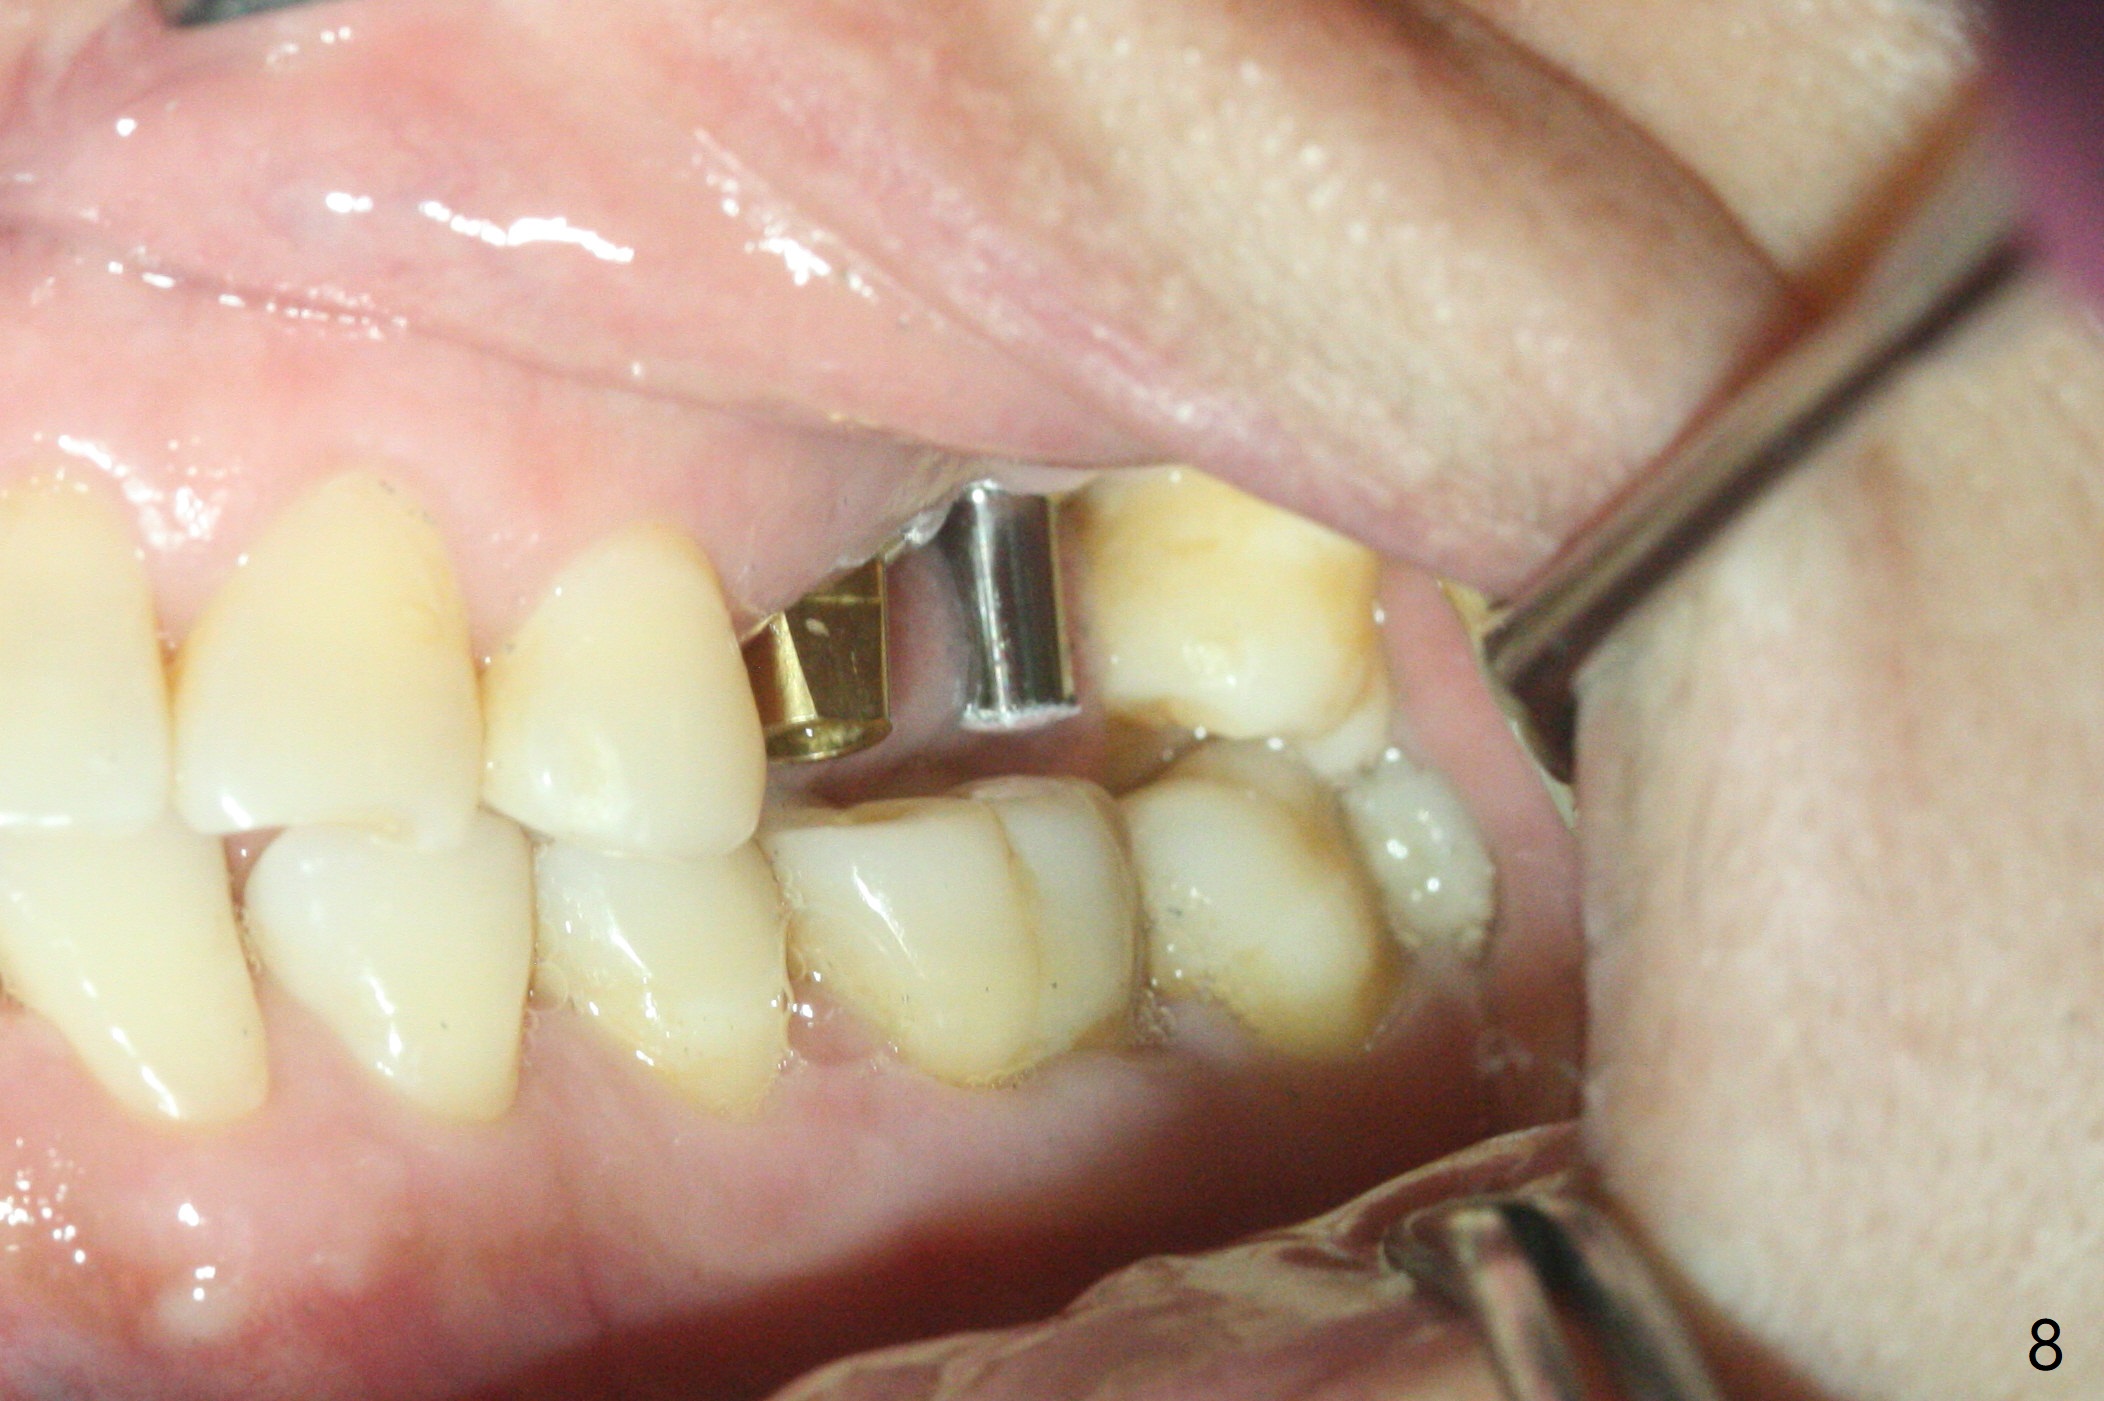

左上六植牙第三次失败后五个月,牙槽嵴宽度尚可,切开后放置导板,3.2乘19毫米园钻头好像接近上颌窦底板(图一),但是粘性骨块和4乘10毫米报废植体就不能进入上颌窦(图二),最后不得不使用3毫米Bicon骨凿,之后同一个报废植体就似乎进入上颌窦(图三),4.5乘8.5毫米正式植体植入深度和稳定性均正常(图四),腭侧植体稍微暴露,放置愈合螺丝后,放置骨粉和PRF膜,缝合,左上5植体放置5.7x4.5(4)毫米基台,固定牙周敷料。术后5.5个月植体好像整合(图五),缺牙间隙特别小,5临时牙冠(P)必须取出才能切开暴露植体,放置5.5x5毫米愈合基台(图六)。伤口愈合后,必须做渐进性负荷,之后做简单局部矫正,推7往远中,6缺失3年,7往近中倾斜移位。两周后牙周敷料脱落,伤口愈合,放置修复基台,故意将基台平面朝远中,足够空间制作临时牙冠(图七)。调整基台长度(比较图七,八)。制作连体牙冠(5,6),有意提高5牙冠高度,使左上7不与对合牙接触,有利于远中移位(图九)。也要在对侧提高咬合(图十)。局部矫正一个月后,磨去右侧咬合垫和磨短左上5,6临时牙冠,前牙还不能完全接触(图十一)。1-2星期前牙开合自行消失,取模做左上5,6牙冠。局部矫正似乎使左上7远中移位大约3毫米(比较图十二,十三)。粘固拧紧后(20 Ncm)14号牙牙冠咬合增高,拍摄根尖片(图十三),两个基台好像仍然完全就位,然后调整咬合。